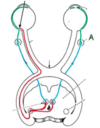

Which congenital heart defect can be identified in this image?

Patent foramen ovale

Atrial septal defect

Patent ductus arteriosus

Ventricular septal defect

Tetralogy of Fallot

Which congenital heart defect can be identified in this image?

Patent foramen ovale

Atrial septal defect

Patent ductus arteriosus

Ventricular septal defect

Tetralogy of Fallot